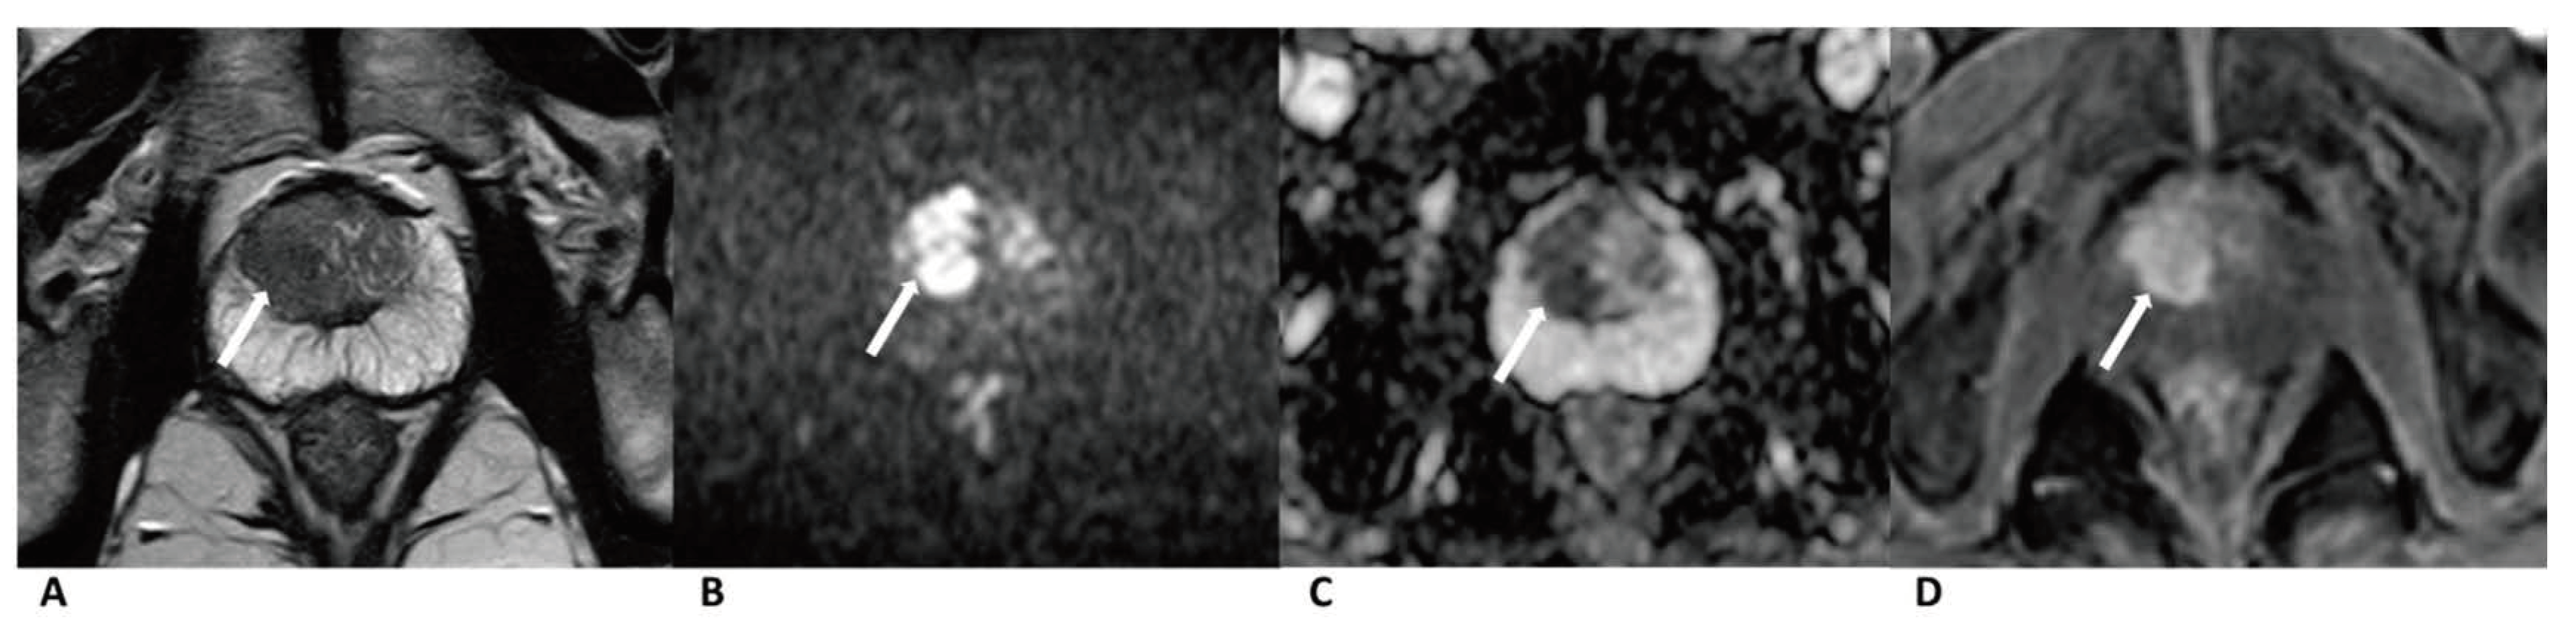

Figure 3. Case of prostate cancer in TZ. Male, 63 years old, prostate cancer with its longest diameter being >1.5cm. T2WI showed a hypointense nodule (arrow) in the right TZ (A). The lesion was hyperintense on DWI (b = 1500 s/mm2) (arrow) and hypointense on ADC images (B,C). Positive enhancement was seen on the DCE (arrow) (D). The lesion was finally assessed as a PI-RADS category 5, indicating that it had a high cancer risk according to PI-RADS v2, PA PI-RADS v2, and biparametric MRI protocols.